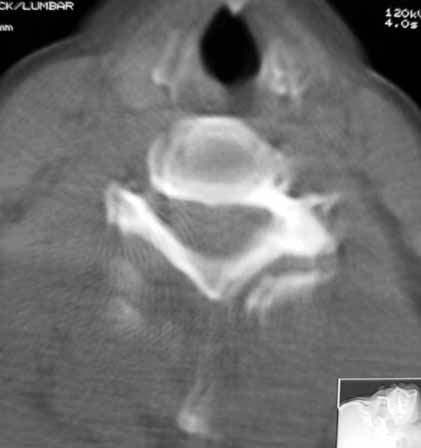

以下是引用zhangzhongshou在2007-4-29 22:53:00的发言:[br]1、c5半脱位,i度前滑脱。[br]2、c5椎板骨折。[br]3、第7幅图像显示右侧椎板骨折,哪一节颈椎,楼主自己知道。[br]4、c2、3附件融合畸形。[br]5、考虑环椎后桥,亦为正常变异。